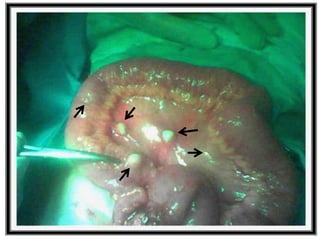

TUBERCULOSIS DIGESTIVA

Cualquier tramo del tubo digestivo puede

resultar afectado por la tuberculosis al

intervenir diversos mecanismos: deglución de

los esputos, diseminación hematógena, la

ingestión de la leche de vacas enfermas de

tuberculosis bovina.

PERITONITIS TUBERCULOSA

Aparece después de una siembra directa de

bacilos tuberculosos procedentes de los

órganos intraabdominales o de unos ganglios

linfáticos con presencia de ruptura, o bien a

causa de una siembra hematógena